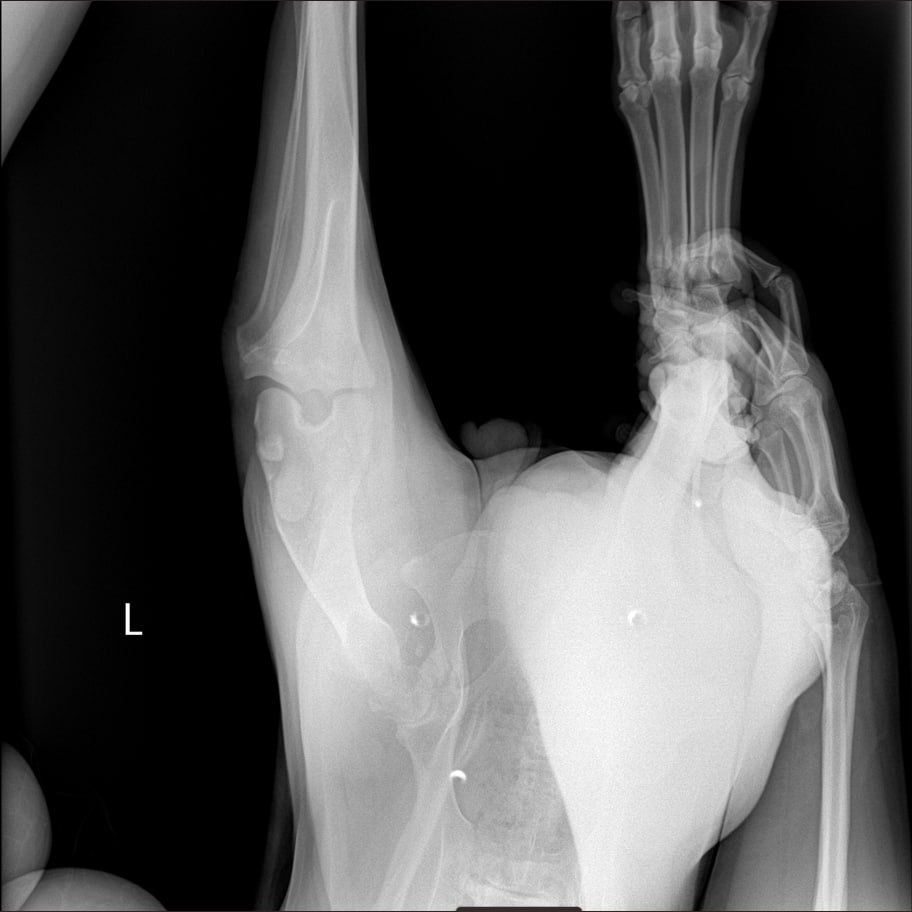

Рентген лапы, которая болит

Сильнейший коксартроз тбс на больной лапе.....который не заметили на первичных осмотрах....зато настаивали в необходимости кастрации. В результате изменения положения лапы, нагрузки - воспаление и боль.